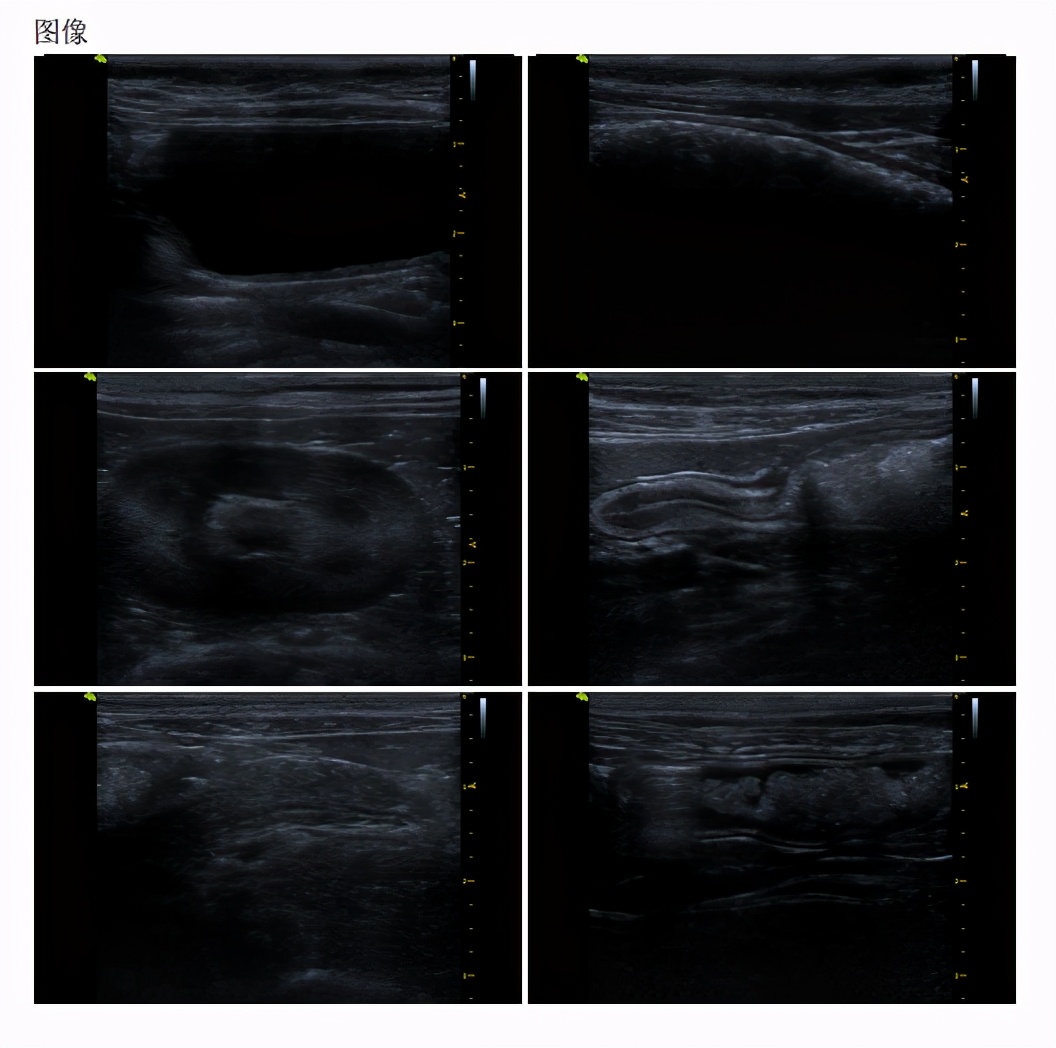

腹部彩超显示无异物,

肠道反应性淋巴结肿大。

胰腺钙化灶。

生化胰腺指标轻微升高